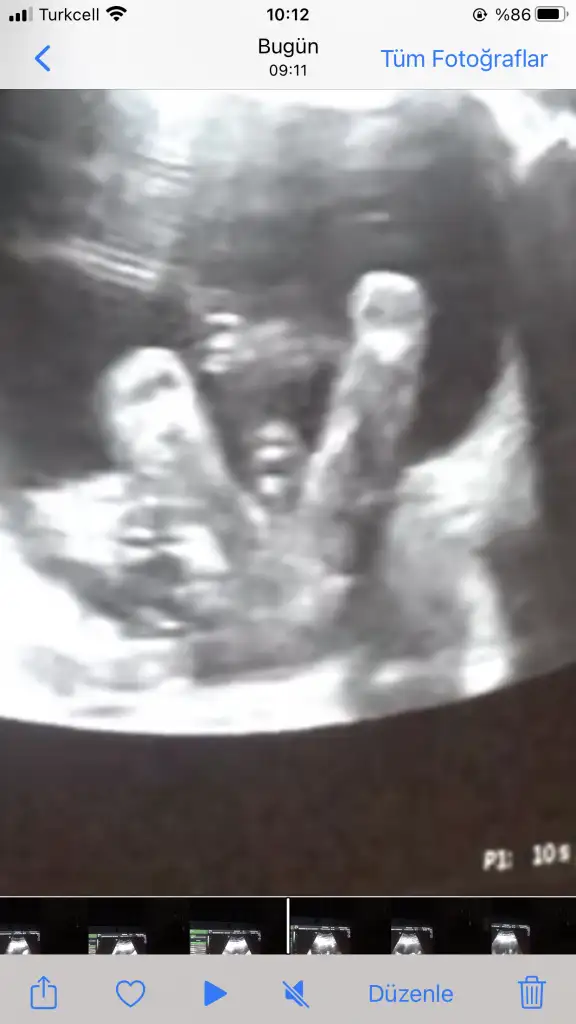

Merhaba Ikra meyra Ikra meyra 11+4te usgmize erkek gibi demiştin. Bugün kontrole gittik bebeğimiz hep poposunu döndü :) bacak arasında da kordon varmış doktor bir türlü emin olup birşey söylemedi. Usg ekliyorum pek nubu görünmüyor gibi ama belki sen görebilirsin :) sonunucu baş aşağı olduğu için onu ters çevirip ekledim. Sana bir fikir veriyor mu acaba 😌

Sizin 11+4 olan usg bakmak isterim bu usgler 15+ bu hafta artık organı oluşmuş nub olmaz